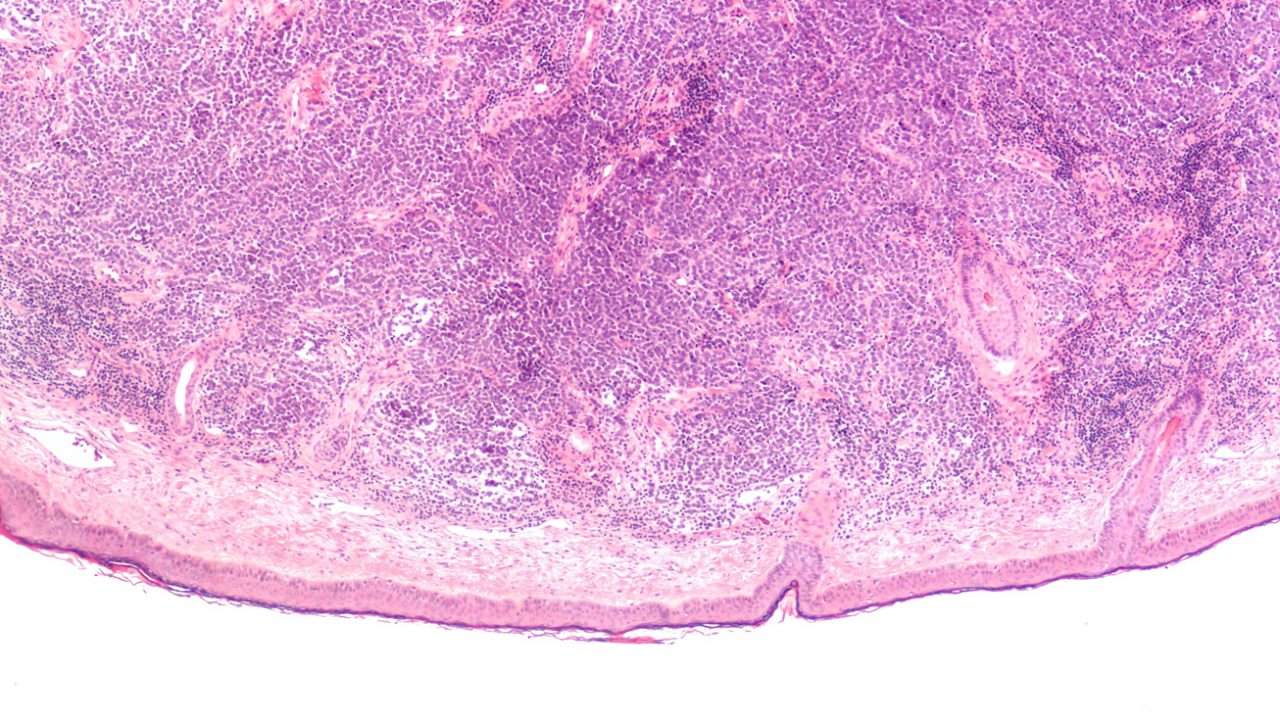

Merkel cell cancer is a rare, aggressive skin cancer, more often fatal than invasive melanoma and basal-cell and squamous-cell carcinomas. Merkel cell carcinoma is composed of cells that look very similar to ‘Merkel’ cells that are a key part of the epidermis, the skin’s outer layer. Normal Merkel cells communicate touch-related information such as pressure and texture to the brain.